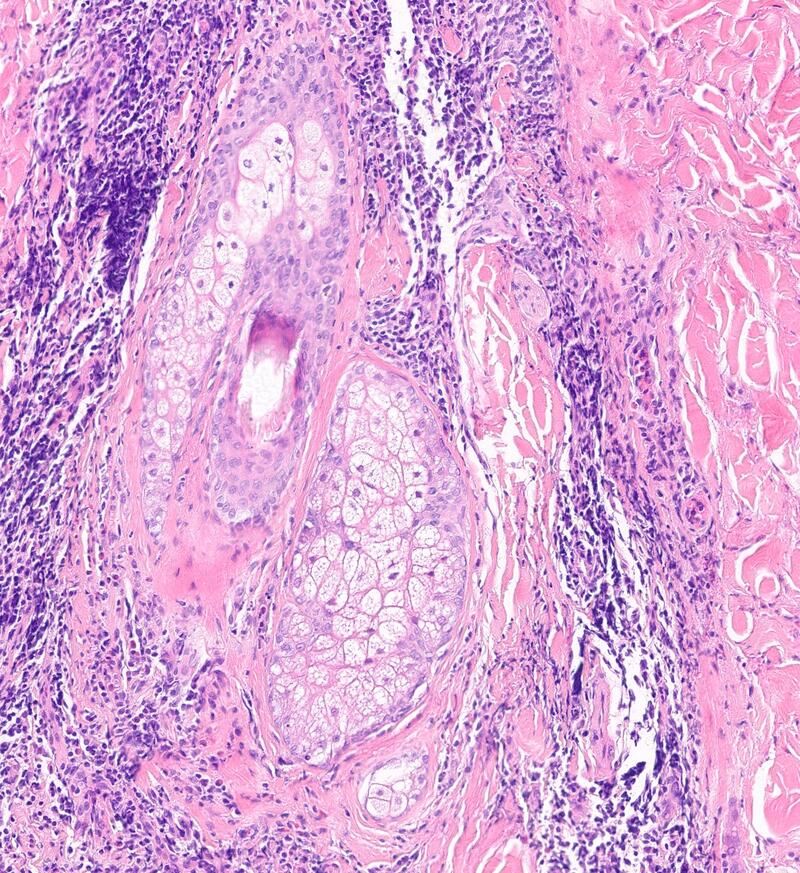

Expert microscopic examination of skin tissue serving dermatologists across Indiana and the Midwest with guaranteed 24-hour turnaround for routine cases.

Melanoma & skin cancers

Inflammatory skin diseases

Autoimmune skin disorders

Nail & hair pathology

and more...

Rapid, definitive DIF for autoimmune and inflammatory skin diseases — results guaranteed within 24 hours.